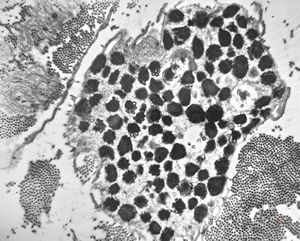

M,41y. | ribosome-lamella complex in tricholeukocyte -hairy cell leukemia, spleen